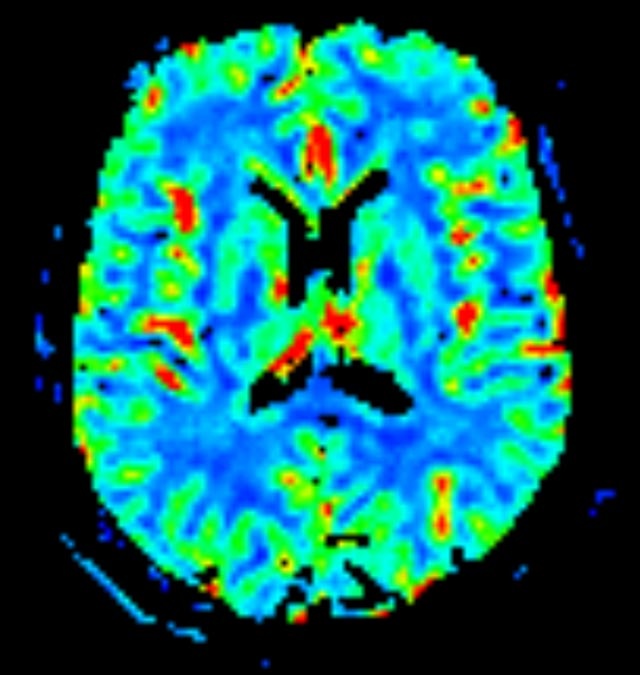

Kopf/Hals

• akute Schlaganfalldiagnostik und chronische Durchblutungsstörungen

• entzündliche Prozesse des Gehirns oder der Gesichtsweichteile

• Tumore

• Abklärung Schwindel, zentrale Sehstörung, Kopfschmerz

• Metastasenverdacht

• Multiple Sklerose

• Abklärung Hirnnerven, Schädelbasis inkl. Hypophyse

• Abklärung Kleinhirn, Hirnstamm, Halsmark

• intrakranielle Gefäße (Abklärung Verschluss, Stenose, Aneurysma)

• Halsgefäße zur Therapieplanung (z.B. Stent, Operation)

Spezialtechniken der Magnetresonanz

• Diffusionswichtung

• Perfusionswichtung

• Suszeptibilitätswichtung

• MR-Spektroskopie